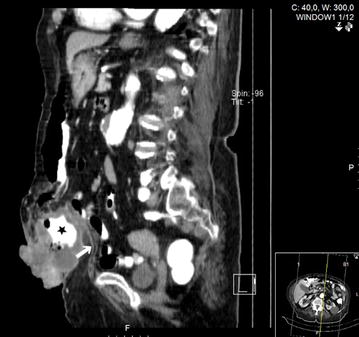

Further investigation with colonoscopy revealed transverse colon cancer; endoscopic biopsy of the tumor and skin punch biopsy confirmed adenocarcinoma of the colon. Thoracic and abdomino-pelvic computed tomography showed a tumoral mass within the umbilical hernia, with cutaneous infiltration (Fig. 2) and enlarged regional lymph nodes, but without distant metastasis—cT4bN0M0.

Fig. 2.

Computed tomography: note the presence of the transverse colon (star) within the hernia sac, outside the muscular layer of the abdominal wall (white arrow)